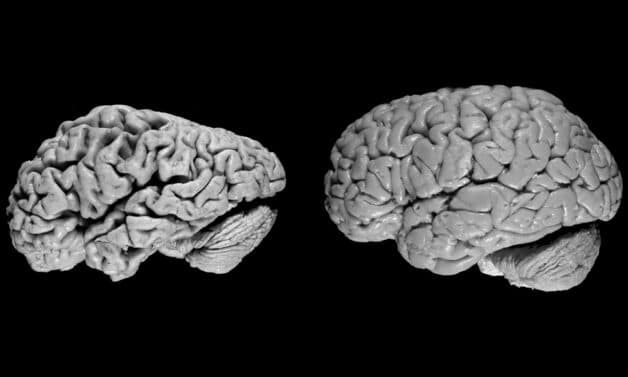

Hình ảnh so sánh não bình thường và não của người bị alzheimer